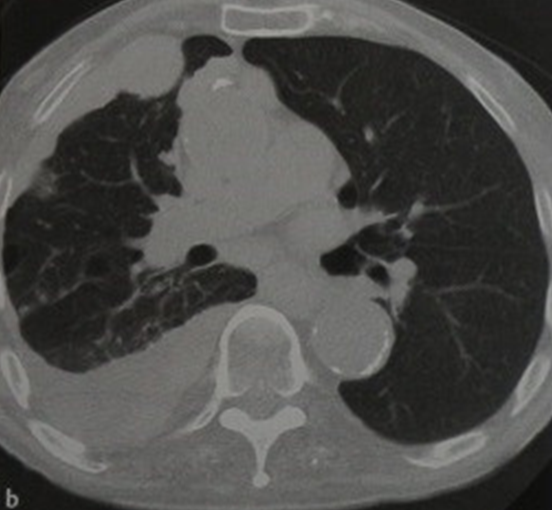

Мезатилиоама справа. Компьютерная томография

В настоящее время для диагностики мезотелиомы, кроме традиционной флюорографии и рентгенографии, широко применяются компьютерная томография (КТ) и магнито-резонансная томография органов грудной клетки и брюшной полости (МРТ). Для морфологической верификации процесса выполняются тонкоигольная биопсия с последующим цитологическим исследованием или трепан-биописия опухоли.

Мезатилиома. Компьютерная томография